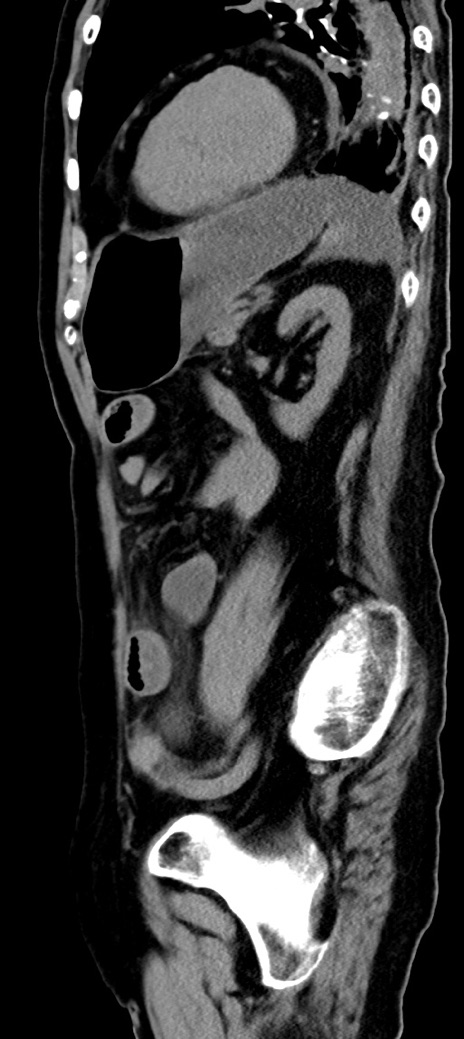

症例40(矢状断像)他院1日前

【症例】90歳代女性

【主訴】腹痛・嘔吐

【現病歴】 食欲低下、嘔吐があり昨日他院受診。肺炎と診断され入院となる。入院後より腹部全体に圧痛あり。胃管留置され経過みていたが、症状持続するため、

当院転院となる。

【既往歴】胸椎圧迫骨折、胆石症

【身体所見】腹部:中央に激痛あり、圧痛あり、反跳痛不明

【データ】WBC 17100、CRP 18.82